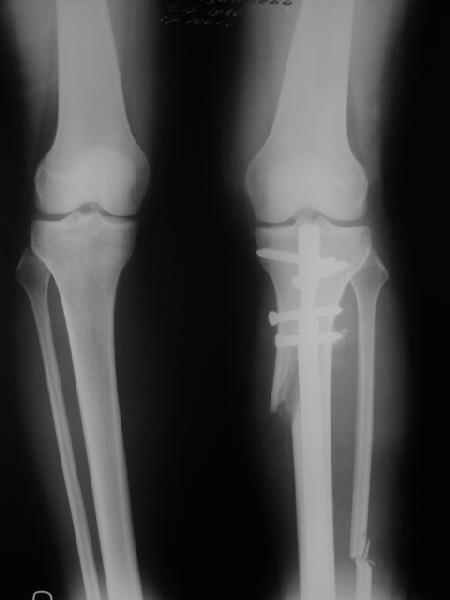

Very nice correction but, to my eye there is some 'over' correction of the tibia, now in some proximal valgus?

. On the right leg you can see some of the tools (from the tool bar above) applied to demonstrate a mild mech-axis varus of about 5 degrees.

On the left the bone landmarks used in the anlaysis are shown.

In essence she has a mild mech-axis varus of 7 degrees with some contribution from the femur (2) degrees and more from the tibia (6 degrees), none from the joint.

Yesterday i performed correction of one leg (the plan to make both in one session was cancelled because of some external reasons). Suggestions of Nuno Lopes were most close to my view. A small wire distractor was used intraoperatively. Derotation ~6-7 degrees was performed also. CT scans evaluating rotation will be available only

tomorrow. No problem to change rotation of the operated limb in the moment of the second surgery. Comments/critics are welcome.

Can the attached result be analyzed by the software?